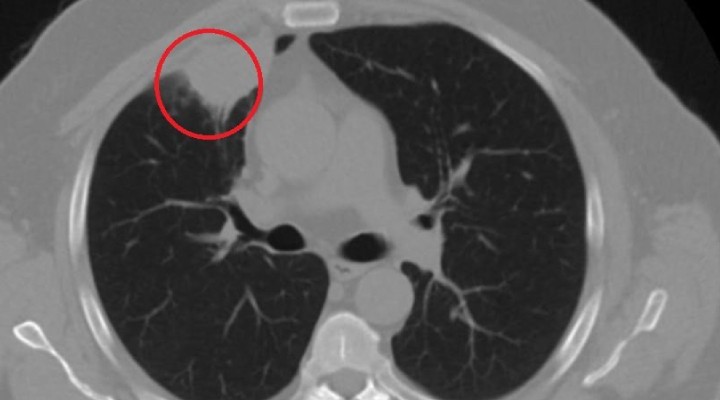

Kent d???nda çal??an N.T.’nin, gö?üs a?r?s? ?ikayetiyle gitti?i hastanede çekilen tomografisinde sa? akci?erinde 4 santimetre çap?nda tümör tespit edildi. Kanser olabilece?i ?üphesiyle yap?lan ileri tetkikler sonras? N. T.’ye akci?er kanseri te?hisi kondu ve acil ameliyat karar? verildi.

– Hastam?z, çal??t??? ba?ka bir kentte gö?sünden darbe al?yor ve a?r?lar? geçmeyince bir üniversite hastanesine ba?vuruyor. Burada hastaya bir akci?er grafisi çekiliyor. Sa? akci?erinde bir kitleye rastlan?yor. Daha sonra hastaya, bir akci?er tomografisi çekiliyor ve gö?üs cerrahisi için önemli büyüklükte olan 4 santimetre çap?nda, akci?er kanserine benzer özellikte radyolojik bulgular olan bir kitle tespit ediliyor. Daha sonra hastaya yap?lan ileri tetkiklerde akci?er kanseri te?hisi konuluyor. Hastaya bir cerrahi planlan?yor.

– 14’üncü gün tekrar bize ba?vurdu ve yap?lan PCR testi negatif ç?kt?. Yeni bir tomografi çektik ve tümörün tamamen ortadan kalkt???n? gördük. ?imdi sonuç bilgilerinden ba?lang?ca gitti?imizde, bu bir akci?er kanseri olsayd?, ortadan kalkmas? mümkün de?ildi. Ba?ka bir patolojiye ba?l? durum olsayd?, yine verdi?imiz tedaviyle ortadan kalkmas?n? çok beklemeyiz. Antiviral tedavisi verdik ve hastan?n radyolojik bulgular? neredeyse tamamen normale döndü. Hastaya bunu izah ettik, ‘Dünya literatüründe hiç görülmeyen bir radyolojik bulgu’ diyerek. Bu gördü?ümüz manzara art?k hastan?n akci?er grafisinde yok, akci?er kanseri de?il.